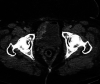

A known consequence of portal hypertension is the development of varices, which are described as "ectopic" when located at unusual sites in the abdomen. Ectopic varices carry a mortality rate as high as 40% after initial hemorrhagic episode. We report a patient who presented with hematuria secondary to bladder varices as the presenting symptom for a new diagnosis of cirrhosis. Cross-sectional imaging, early recognition of this rare event, combined with multidisciplinary management was essential for this patient to have a successful outcome.